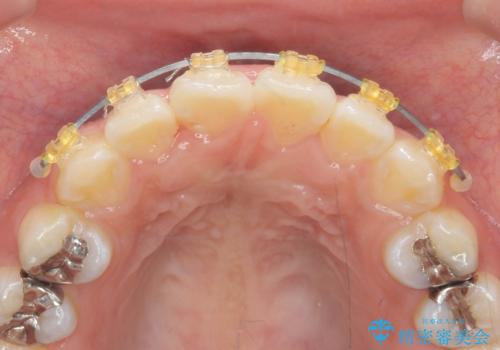

- 矯正装置

- インビザライン

マウスピース矯正を始める前に、ねじれを取るのが短期間で済む部分ワイヤー小矯正を行うことで、全体的な治療期間を短くする治療計画を実行していきます。